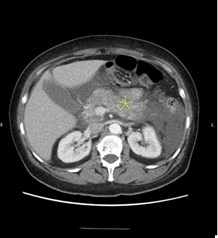

of acute cardiopulmonary disease. CT scan of the abdomen and pelvis with IV

contrast showed acute pancreatitis with extensive fluid and peripancreatic

inflammatory changes throughout abdomen and possible developing ileus (Figure

1A and 1B). However, no evidence of gallstone or biliary dilatation or

Figure 1A and 1B: CT scan image of showing

inflammation of pancreas (Yellow Star)